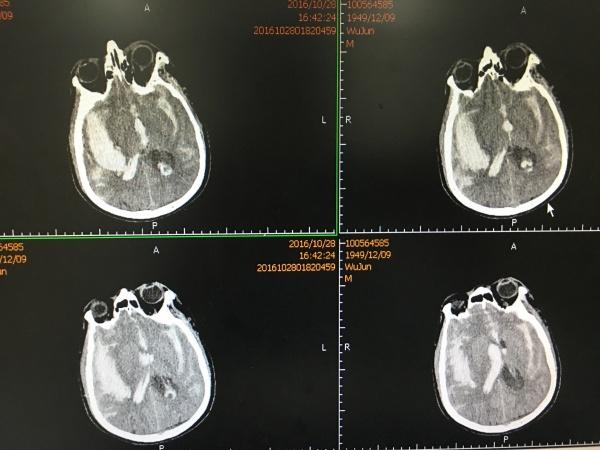

再过一周,再次复查CT示:

硬膜下积液较前稍增加,中线基本回位,积液未造成明显占位效应,故我们决定继续观察,必要时可以予以Ommayya囊植入、积液引流术。

患者现病情平稳,我们很有信心现状可进一步改善。